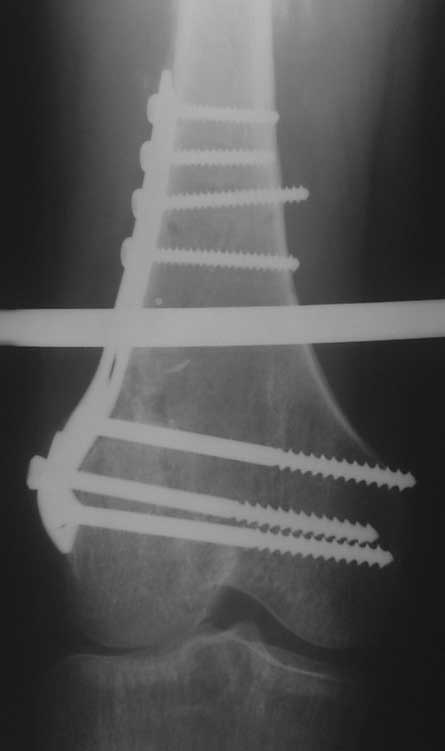

Уважаемые коллеги, помогите пожалуйста с тактикой лечения. Больная 43 лет, подвернув правую ногу, получила простой (А2) перелом правого бедра в с\3, м\у установленными ранее пластинами. В течении 4 недель лечится методом скелетного вытяжения.В анамнезе: в июне 2011г. получила перелом наружного мыщелка правого бедра на фоне консолидированного в порочном варусном положении перелома вертельной зоны (со слов травма 5 лет назад - лечилась консервативно), сопровождающимся укорочением 5 см. В одну операционную сессию выполнен остеосинтез перелома мыщелка бедра Т-образной пластиной и с целью коррекции укорочения выполнена вальгизирующая межвертельная остеотомия с фиксацией клинковой пластиной.На наш взгляд, наиболее простым является накостный остеосинтез диафизарного перелома по передней поверхности бедра, но смущает необходимость образования в последующем дополнительного кожного рубца. Пожалуйста, может быть у Вас есть другие мнения. Зарание благодарен. С уважением А.Гринь. ОКБ №2 г.Тюмень.

М\У пластины - наверное слово между пластинами, зачем такие сокращения не понятно. Хотя боковых рентгенограмм нет, можно предполагать что мыщелки бедра с июня вероятно в стадии активноой консолидации. В связи с чем в большей мере согласен с Челноковым А.Н. и удалил бы старые фиксаторы перейдя к блокироанному бедренному гвоздю с дистальной полиаксиальной фиксацией. Если есть какие-нибудь осложняющие моменты то аппарат Илизарова более выгоден пациенту, чем третья пластина.

На снимке положение клинка идеальное, но шейка в ротации. Из-за неправильного расчета остеотомии не удалось латерализовать диафиз, и конечность находится в чрезмерном вальгусе. При укорочении с вальгусом увеличивает стресс в зоне между пластинами, и конструкция не выдерживает, и при малой травме может осложниться стрессовым переломом.

Расположение клинка и степень сращения в зоне остеотомии трудно увидеть по одной проекции, и поэтому желательно дополнить исследования КТ и боковыми рентген снимками.

Из возможных операций: я бы предложил провести ретроградную фиксацию бедра после удаления дистальной пластины. При отсутствии полного сращения перелома можно установить пару шурупов спереди и сзади гвоздя, или можно оставить укороченный вариант пластины.